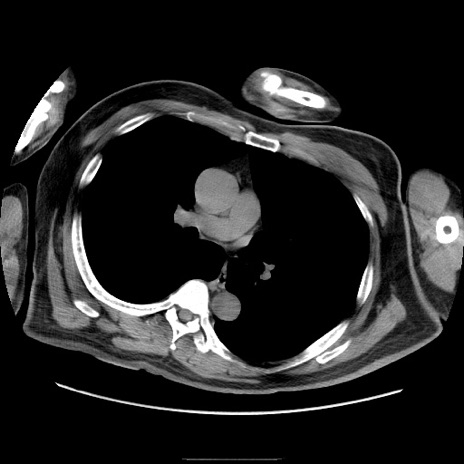

症例22(横断像)

【症例】50歳代男性

【主訴】腹痛

【現病歴】AVMからの被殻出血のため回復期リハ病棟入院中。 本日午後3時頃急に下腹部痛が出現した。

【既往歴】AVM、被殻出血、虫垂炎、高血圧

【身体所見】意識晴明、左半身不全麻痺、会話の理解は良好、36.5°C、腹部:膨隆、全体に板状硬、下腹部正中に圧痛点あり、反跳痛-、筋性防御不明、右下腹部にope scar

【データ】WBC 9400、CRP 0.06